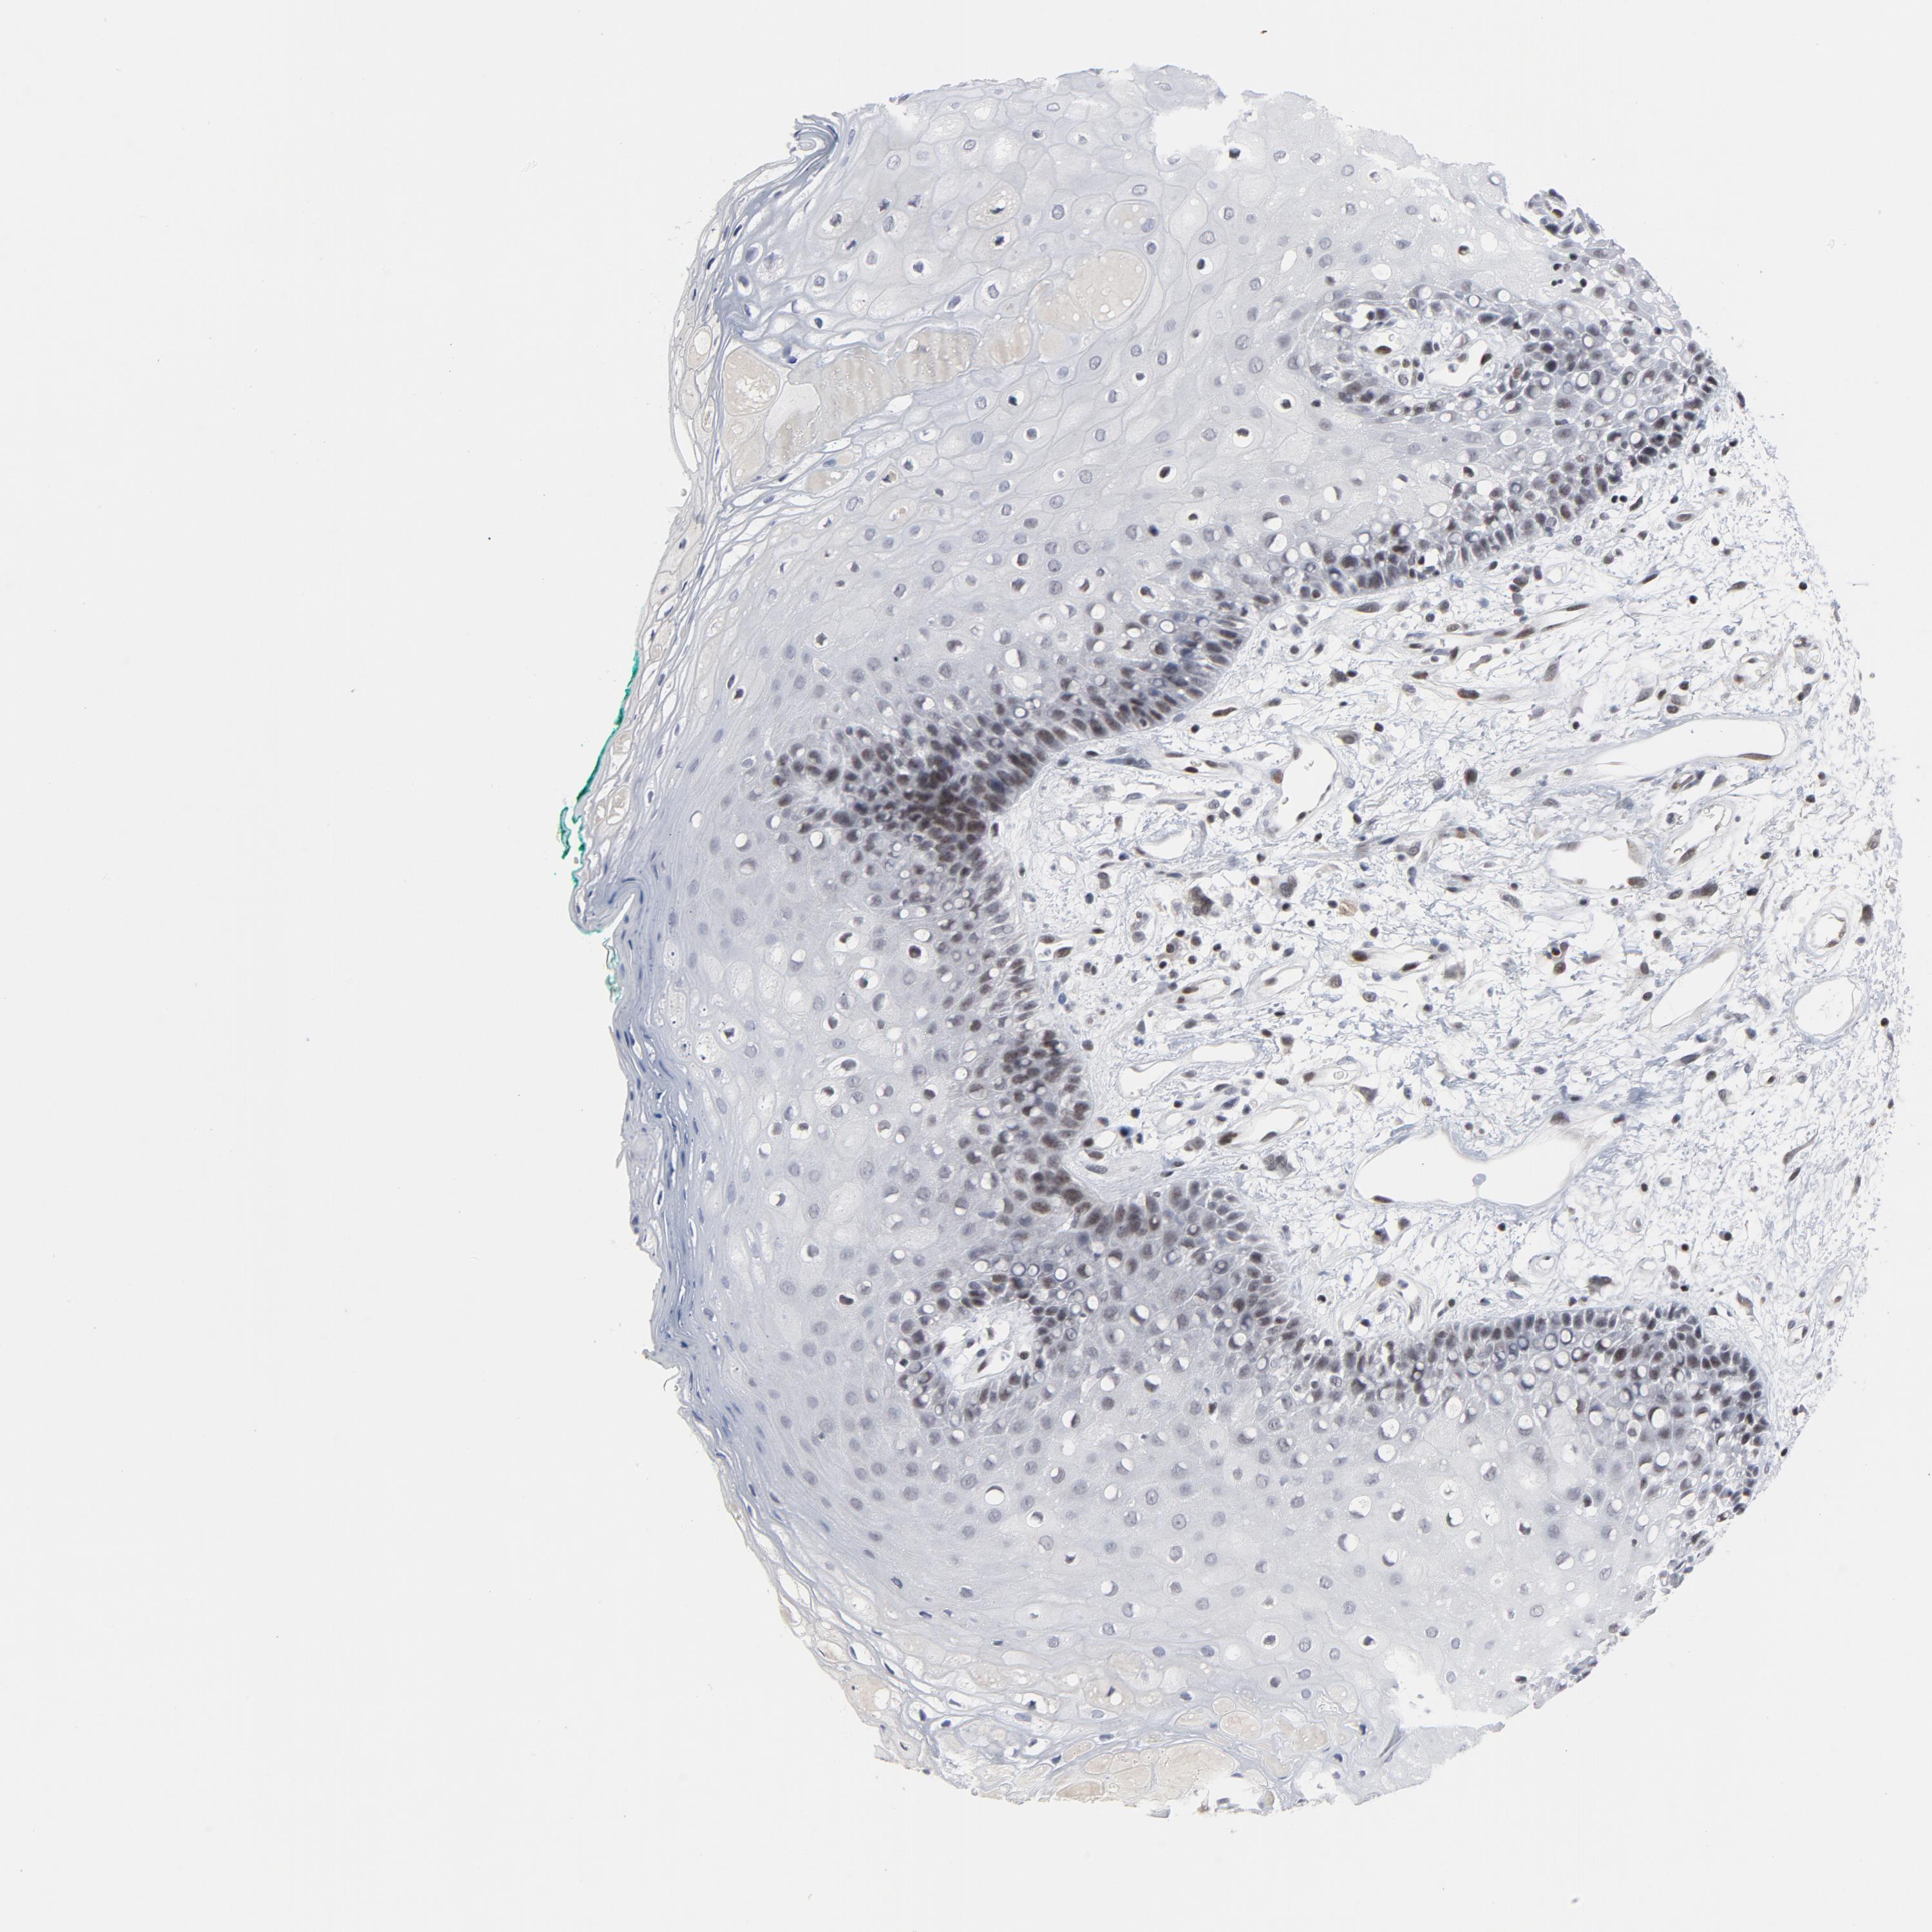

TISSUE PRIMARY DATA ORAL MUCOSA Show tissue menu

Oral mucosa

ORAL MUCOSA - Antibody stainingi

Antibody staining in the annotated cell types in the current human tissue is reported as not detected, low, medium, or high, based on conventional immunohistochemistry profiling in selected tissues. This score is based on the combination of the staining intensity and fraction of stained cells.

Each image is clickable and will lead to virtual microscopy that enables deeper exploration of all samples and also displays staining intensity scores, fraction scores and subcellular localization as well as patient and tissue information for each sample.

Antibody HPA003258Antibody HPA028791Antibody CAB004411

Squamous epithelial cells MediumMediumNot detected